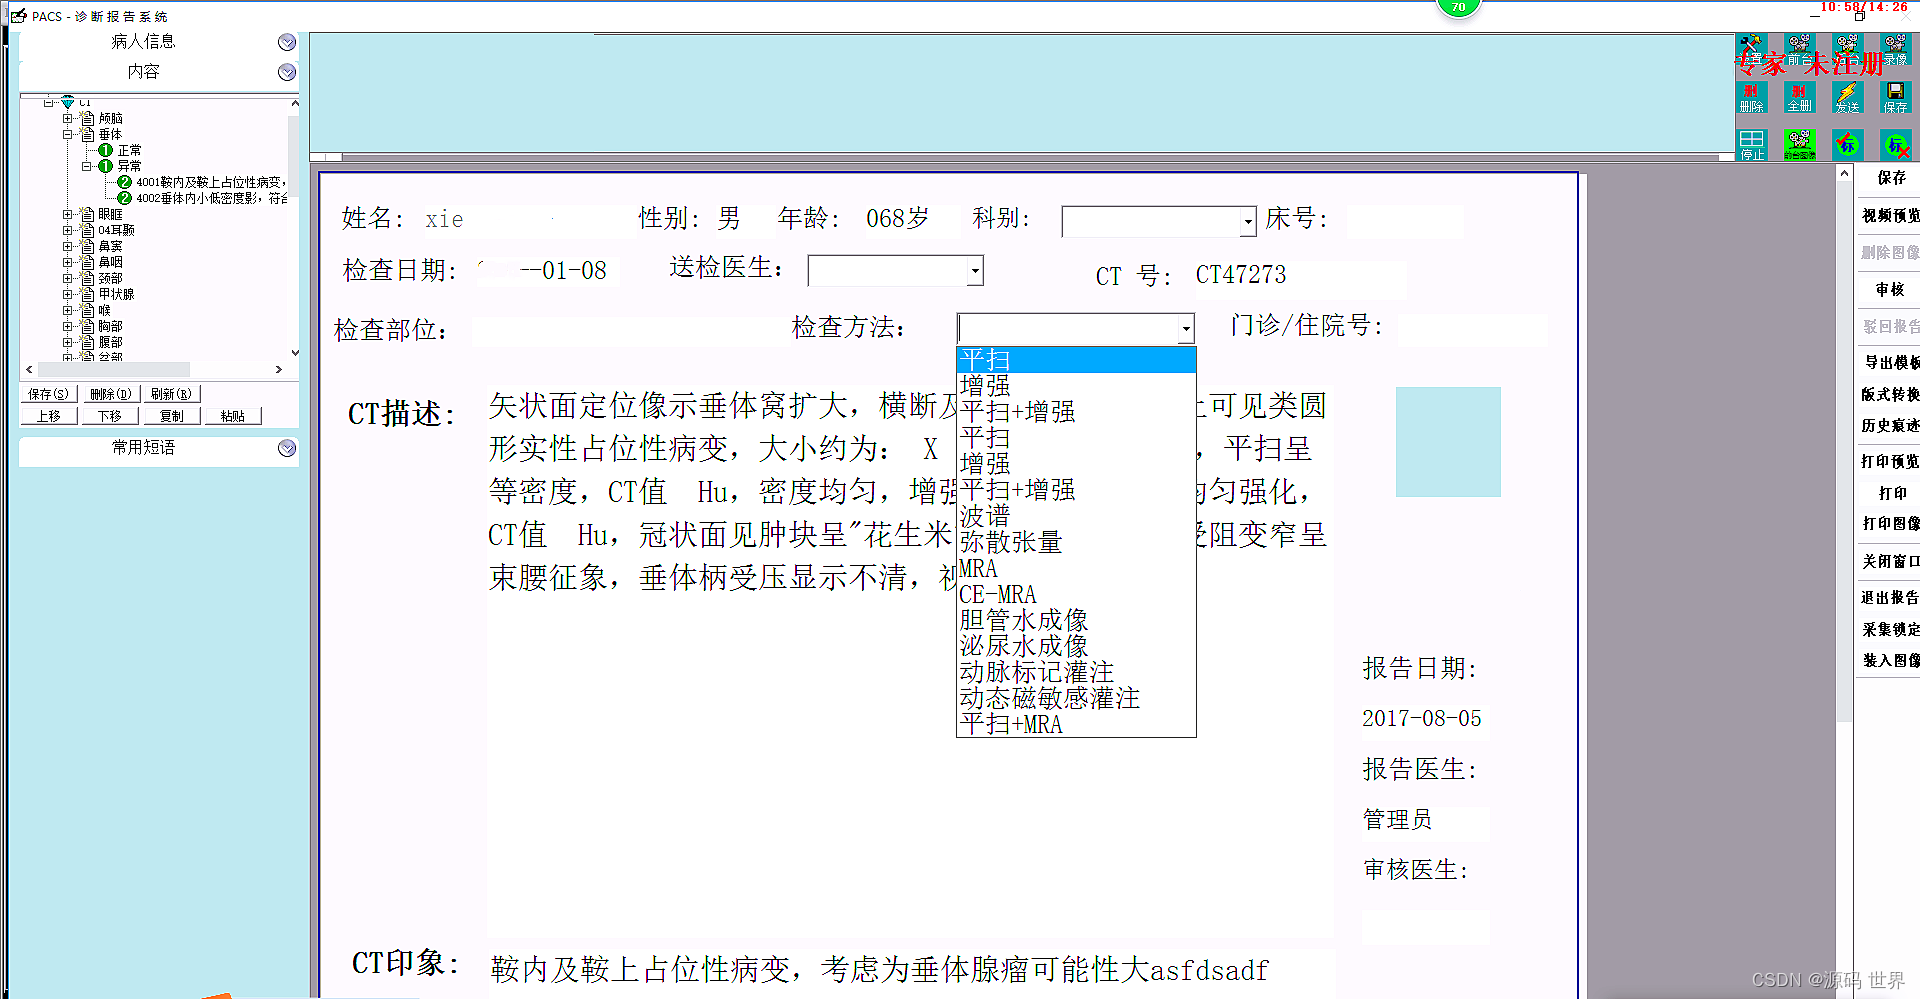

放射信息系统(RIS)主要用于管理和调度患者的放射检查流程。它的主要功能包括患者管理、检查预约、报告生成等。RIS系统通常作为独立系统运行,侧重于临床流程管理,并优化放射科的工作流程。

影像归档与通信系统(PACS)则专注于影像资料的存储、检索、分发和通信。PACS系统可以联接不同的影像设备(如CT、MR、XRAY、超声、核医学等),存储和管理图像,以及图像的调用与后处理。PACS系统也可以与其他系统如HIS、RIS集成,以提高工作效率和检查准确性。

RIS系统和PACS系统虽然在一些方面有所重叠,但它们各自承担着不同的核心职能。RIS系统更多地关注于放射科内部的流程管理,而PACS系统则致力于影像资料的高效存储和交流